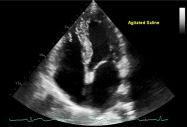

- Bảng 7. Siêu âm cản âm bằng nước muối sinh lý được tạo bọt (sagitated saline)

Bảng 7. Siêu âm cản âm bằng nước muối sinh lý được tạo bọt (sagitated saline)

| Cửa sổ siêu âm từ mỏm tim Mặt cắt 4 buồng | · Nhĩ phải (RA) · Thất phải (RV) · Nhĩ trái (LA) · Thất trái (LV) · Vách liên nhĩ (IAS) | |||

| 7.1a. (Video 87)

| Ghi hình động trong 20 nhát bóp (beat) trong trường hợp có shunt do thấm lỗ bầu dục (PFO) Mặt cắt 4 buồng từ mỏm với góc của chùm siêu âm tối ưu Các nhát bóp đầu tiên chưa có bọt cản âm | |||

| 7.1b. (Video 87)

| Beat 1: Bọt cản âm lấp đầy các buồng tim Bắt đầu đếm số nhát bóp khi nhĩ phải và thất phải được bọt cản âm lấp đầy Mũi tên chỉ vào hình ảnh phình vách liên nhĩ về phía nhĩ trái | |||

| 7.1c. (Video 87)

| Beat 4: những bọt cản âm đầu tiên tại vách liên nhĩ (mũi tên) xuất hiện trong vòng 6 beat kể từ khi các buồng tim phải được cản âm. Điều này cho thấy có shunt phải – trái trong tim. | |||

| 7.1d. (Video 87)

| Beat 16: HÌnh ảnh buồng nhĩ trái và thất trái trống âm do các bọt cản âm được tiêm bolus đã hoàn thành chu trình sau khi đi qua nhĩ phải và thất phải. Điều này cho thấy không có shunt ngoài tim | |||